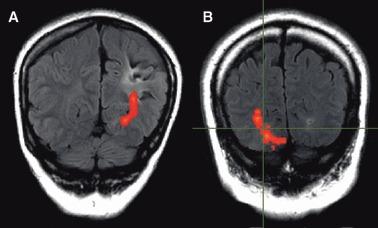

About one-third of patients with epilepsy are refractory to medical treatment and may be amenable to surgery. However, in patients with lesions on or near the presumed course of the optic radiation, the potential benefits of resection must be balanced against the risk of a visual field deficit. This study demonstrates the utility of diffusion tensor imaging (DTI) tractography in delineating the course of the optic radiation and its relationship to the epileptogenic lesion prior to epilepsy surgery.

Anatomic and DTI scans were acquired on 10 patients with medically refractory epilepsy undergoing presurgical evaluation at the National Hospital for Neurology and Neurosurgery. Five patients underwent surgery and repeat scans postoperatively. The optic radiation was delineated and visualized in relation to the lesions on anatomic images and in three-dimensional (3D) reconstructions. Preoperative and postoperative visual fields were acquired by Goldmann perimetry.

The entire optic radiation was reliably delineated bilaterally in all patients. The results provide helpful additional information in informing the patient of the risks of surgery and in planning the surgical procedure and approach. Postoperative imaging findings correlated with the visual field data.

The optic radiation shows significant anatomic variability, but can be reliably delineated by tractography. Because surgical disruption of the optic radiation has serious consequences for the patient, DTI tractography is a useful technique in this population. Future integration with real-time neuronavigation will minimize the risks of neurosurgery.